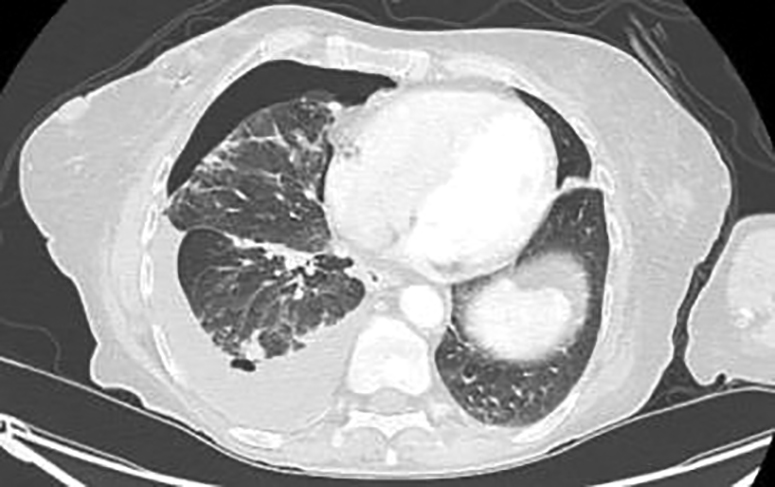

Initial thoracentesis performed on 05/08/2025 drained 2 L of pleural fluid. The pleural fluid analysis showed lymphocyte predominance, consistent with an transudative process (WBC 344, Protein 4.2, LDH 161, Glucose 103), and was negative for malignancy. Despite this, imaging (CT chest, abdomen, and pelvis) revealed a right-sided hydropneumothorax, diffuse bilateral pulmonary nodules (up to 8.9 mm), and air foci within the effusion, raising concern for empyema or metastatic disease (Figure 1).

Figure 1

Figure 1. CT Chest – Axial view showing a large right-sided hydropneumothorax with adjacent air-fluid levels. Multiple bilateral pulmonary nodules (up to 8.9 mm) are visible. The presence of air foci within the pleural space raised concern for empyema versus metastatic disease.